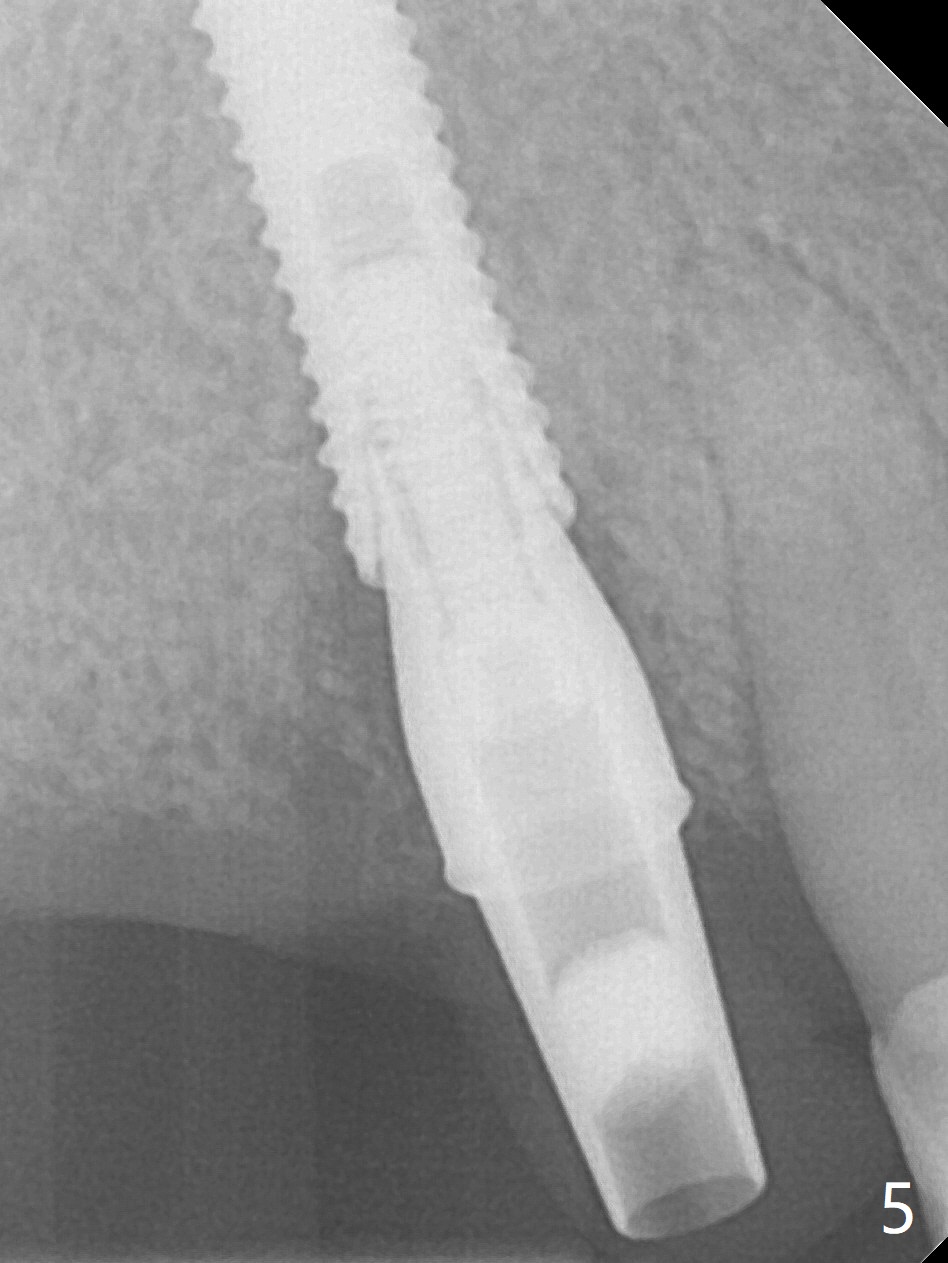

Soft Bone: Underprep and Longer Implant

Extraction of the tooth #5 with mobility III reveals no buccal plate and low palatal plate. Osteotomy starts as palatal as possible (Fig.1). The bone density is low. After use of 2.7 mm drill (Fig.2), a 3 mm drill can be inserted into the osteotomy without resistance. A 4x16 mm implant is placed with insertion torque <30 Ncm. When an abutment is placed, the implant is found to have been placed distal. The implant is untorqued for change in trajectory. When a 4.5x7(5) mm abutment is placed, the abutment turns with the underlying implant (Fig.3). The former is kept to be turned with a hand driver until the latter is unable to turn. Following placement of allograft (Fi.g3,4 *), a mini-provisional is fabricated to retain the bone graft and at the same time not to be interfered with when a flipper is in and out. The bone graft in the former socket gap appears to have integrated into the native one 4.5 months postop (Fig.5).